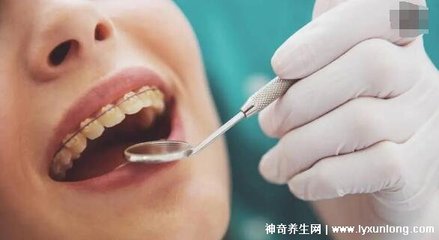

洗牙也叫洗牙。目前常用的是超声波洁治。超声波洁牙器由超声波发生器和换能器组成。发电机发出电磁振动,换能器将高频电能转化为超声波振动。通过换能器上工作头的高频振动,去除附着在牙齿表面的牙垢。洗牙后会抛光,可以让牙齿更光滑,减少洗牙后的牙本质过敏。有些患者在洗牙过程中会出现牙龈出血的情况,所以要选择消毒设施完善的医疗机构进行洗牙。

洁牙,俗称洗牙,专业术语龈上洁治,是指用洁治器械清除牙龈上的牙菌斑、牙菌斑和色斑,抛光牙齿表面,延缓牙菌斑和牙结石的再沉积。菌斑和牙结石是牙周病最重要的局部刺激因素,洁治是清除龈上菌斑和牙结石最有效的方法。洗牙后,牙齿会对冷热有点敏感,感觉酸痛。这种暂时的症状和原来的出血情况一般会在一周左右消失。如果酸痛症状持续,可以考虑市面上的防敏感牙膏,一个多月后会有所改善。

1。首先要做初步检查。医生会对口腔内的牙结石、牙菌斑,或者是否有牙周炎等进行治疗。,而且通常会先推荐使用一些辅助漱口水,所以如果有这样的建议,就要遵医嘱使用3~4天。但这种漱口水不能长期使用,只能短时间缓解和消除部分牙龈症状,然后才适合洗牙。2.洗牙后,牙齿会有一个短暂的敏感期,经常会让洗牙者觉得牙齿冰凉,甚至有的洗牙者会觉得牙齿变宽。这些都是去除牙菌斑和牙结石后的敏感特征。后来这种敏感症状会逐渐减轻,大部分需要一周左右。注意这段时间不要吃生冷硬的食物。

洗牙可以去除沉积在牙龈上的牙垢、牙菌斑和色素,打磨牙齿表面,减少牙菌斑和牙垢的沉积。同时能有效缓解牙龈炎、牙周炎,有益口腔健康。洗牙的缺点:1。洗牙会去除牙缝里的牙垢,导致牙缝变宽;2.洗牙操作不当会在牙齿表面留下微小划痕;3.洗牙后牙齿会变得更加敏感,不注意清洁牙齿可能会加重病情。洗牙的利与弊,俗称洁牙,专业术语龈上洁治是指用洁治器械清除牙龈上的牙菌斑、牙菌斑和色斑,打磨牙齿表面,延缓牙菌斑和牙结石的再沉积。菌斑和牙结石是牙周病最重要的局部刺激因素,洁治是清除龈上菌斑和牙结石最有效的方法。洗牙的主要目的是预防和治疗口腔疾病,而不仅仅是为了好看。牙龈炎和牙周炎的炎症可以通过洗牙来缓解,但牙周炎不能单靠洗牙来治愈,洗牙后还要进行进一步的专业治疗。洗牙后两周,不宜吃寒、热、酸、甜等食物。洗牙后,牙齿会对冷热有点敏感,感觉酸痛。这种暂时的症状和原来的出血情况一般会在一周左右消失。如果酸痛症状持续,可以考虑市面上的防敏感牙膏,一个多月后会有所改善。3、洗牙对牙齿有没有危害